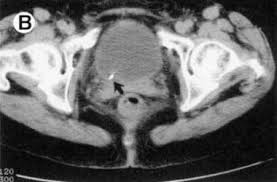

Diagnostic Accuracy Of North America Expert Consensus Statement On Reporting Ct Findings In Patients Suspected Of Having Covid 19 Infection An Italian Single Center Experience Radiology Cardiothoracic Imaging

Diagnostic Accuracy Of North America Expert Consensus Statement On Reporting Ct Findings In Patients Suspected Of Having Covid 19 Infection An Italian Single Center Experience Radiology Cardiothoracic Imaging from pubs.rsna.org